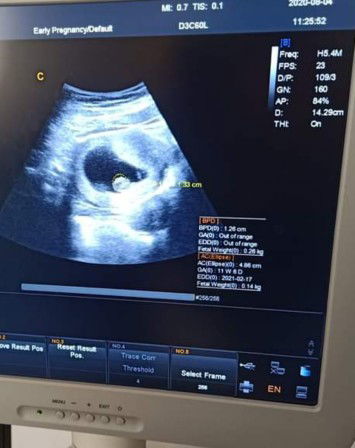

Hpl nya yg mna y bun ??

Yg tulisan EDD bun, itu kann tgl 17-02-2021